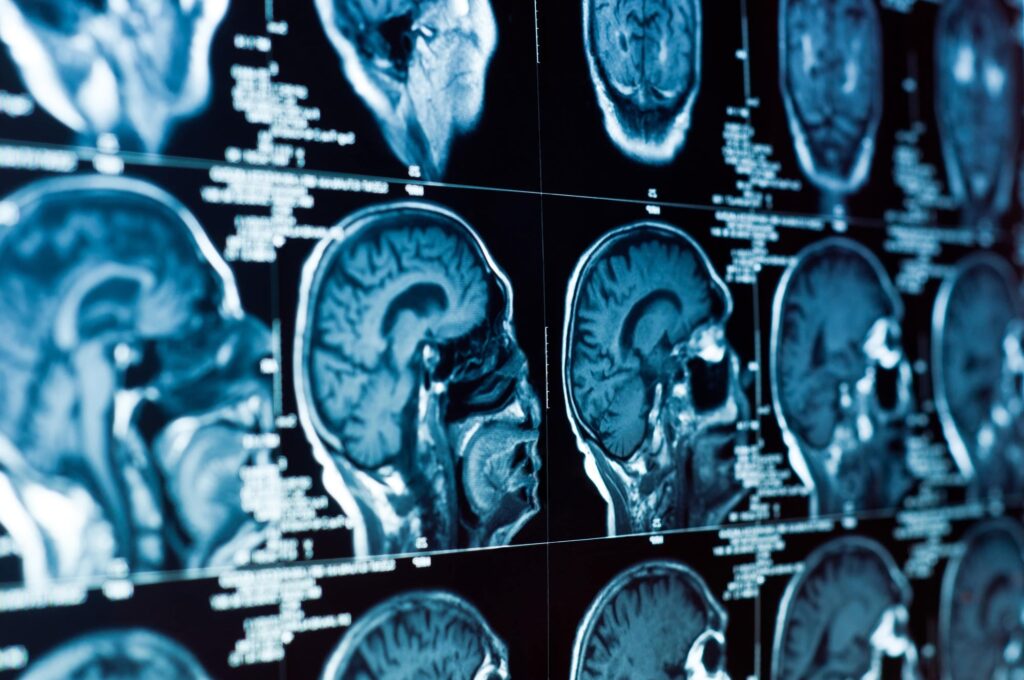

1. Injuries Aren’t Visible On Standard Imaging

Mild to moderate traumatic brain injuries often don’t appear on CT scans or MRIs. The structural damage might be microscopic, but the functional impairments are real and devastating.

Insurance companies use negative imaging to deny claims or minimize damages. They argue that if nothing shows on the scan, the injury must not be serious. This completely misunderstands how brain injuries work.

We work with neurologists, neuropsychologists, and other professionals who can document brain injuries through cognitive testing, functional assessments, and advanced imaging techniques like diffusion tensor imaging. This medical evidence proves injuries that insurance companies want to deny.